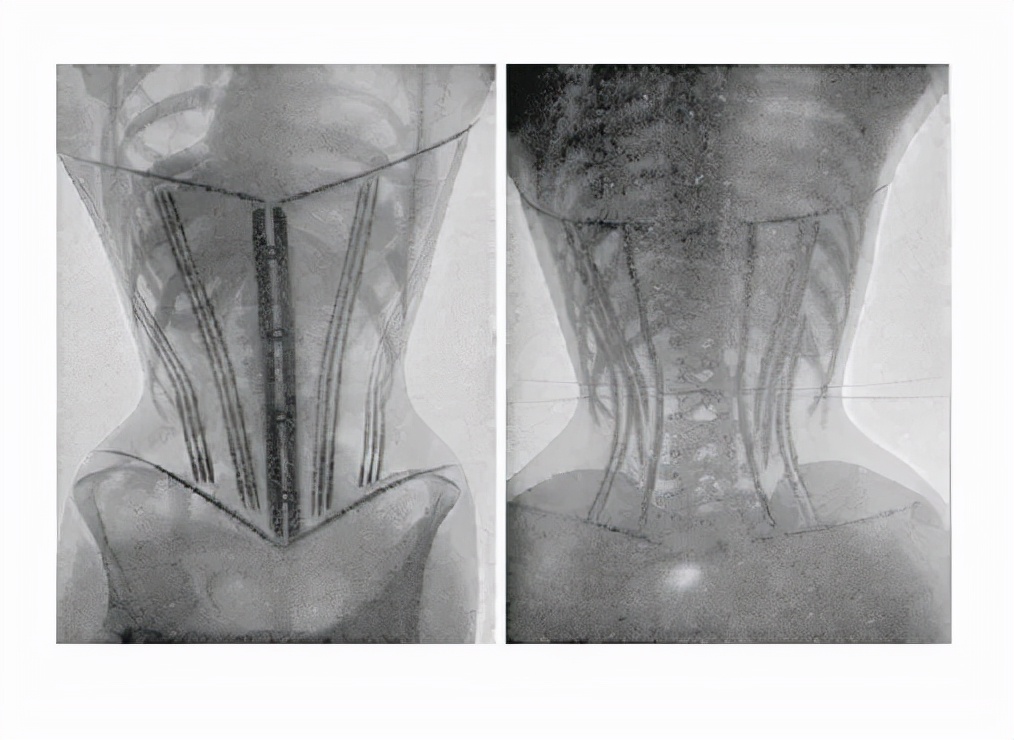

收腹带种类很多,有纱布式的、松紧带式的、*裤内**式的、腰带式的,但基本原理都是一样的,加快恶露排尽。